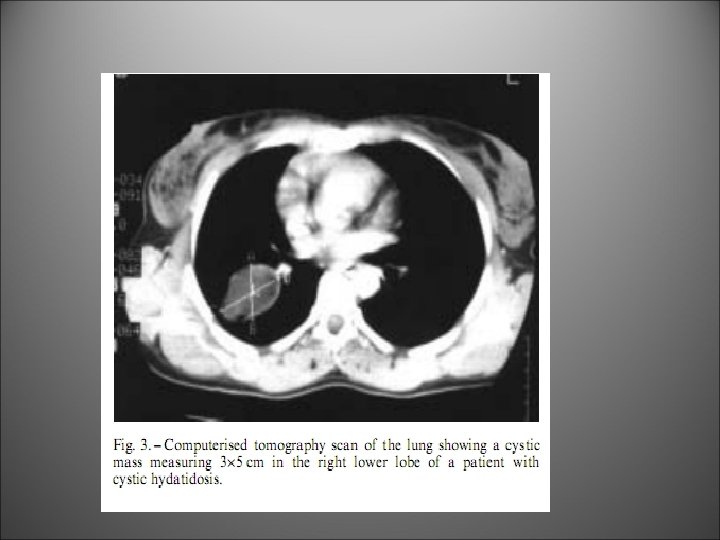

A patient with bilateral hydatid cyst